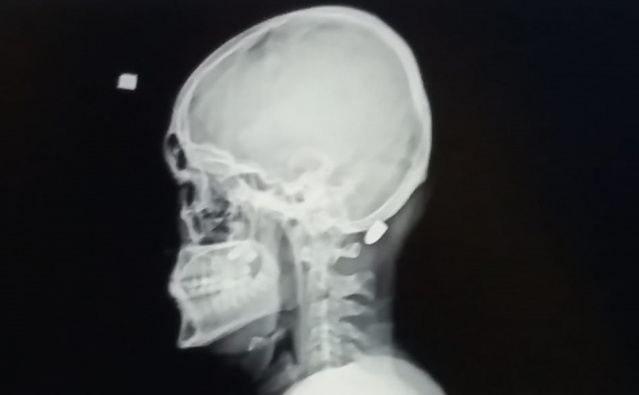

Trabzon'un Vakfıkebir ilçesindeki Karadağ Yaylası'nda önceki gün saat 14.00 sıralarında babası ve amcası ile birlikte yaylada bir evin dış cephe kaplamasını yapan 18 yaşındaki Ali Kuleyin'in başına nerden atıldığı belli olmayan kurşun isabet etti.

İlk önce kurşun olduğunu anlamayan genç, elini başına götürdüğünde kan geldiğini anlayınca ailesine haber verdi. Ailesi tarafından Vakfıkebir Devlet Hastanesi kaldırılan gence isabet eden yorgun mermi başarılı bir operasyonla saplandığı yerden çıkartıldı. Tedavisinin ardından taburcu edilen Kuleyin'in başına isabet eden merminin hangi tabancadan çıktığının belirlenmesi için balistik incelenmeye gönderildi.